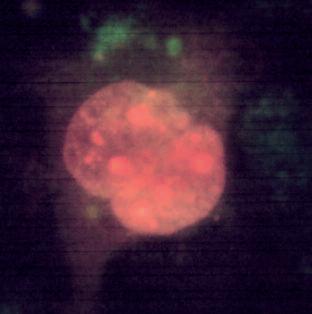

Immagine al microscopio di cellule leucemiche. Le sfere rosse del pacmen rappresentano gli enzimi collagenasi.

Questo vale anche per le cellule leucemiche. Una caratteristica di questa forma di tumore del sangue è l’eccesso di produzione di globuli bianchi, i pazienti affetti da leucemia muoiono principalmente, perché queste cellule bloccano la circolazione del sangue. In molti casi i leucemici muoiono per il cedimento di vari organi, in particolare ‘gli organi filtro’: il fegato e la milza. Milioni di globuli bianchi invadono questi organi attraverso il flusso sanguigno. Queste cellule cancerose producono immense quantità di enzimi che digeriscono il collagene, digerendo letteralmente questi organi dall'interno.

La foto nella pagina a fianco mostra una sezione trasversale al microscopio del fegato di un paziente con ‘leucemia linfatica’. Ciascuno dei piccoli puntini viola nella foto è un globulo bianco (in questo caso linfocita) che ha invaso il tessuto del fegato (aree rosa).

Considerando l’enorme quantità di questi puntini viola e il numero di enzimi che assimilano il collagene che ciascuno produce, è facile prevedere l’ingente distruzione del tessuto connettivo e il danno apportato all’organo da questo tipo di cancro.

La leucemia è un buon esempio di come la comprensione dei meccanismi delle cellule tumorali, la produzione di enzimi che digeriscono il collagene da parte dei globuli bianchi, per poter studiare terapie efficaci.

Immagine al microscopio della leucemia linfatica

Globuli bianchi affetti di cancro (linfociti) invadono il fegato L’enorme quantità di collagenasi prodotte da queste cellule distruggono l’organo e causano insufficienza epatica.